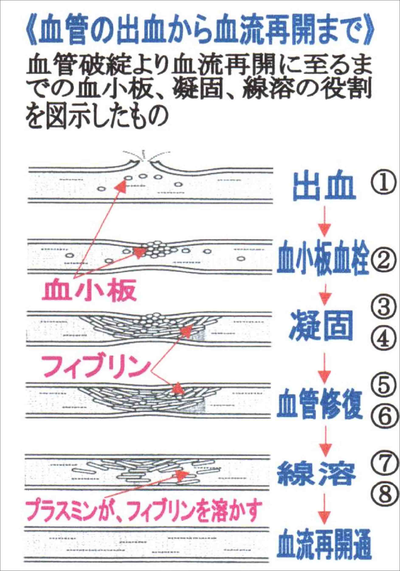

血液凝固と線溶こんにちは✨薬剤師ロクガツです。 今回は血液凝固と線溶系についてのまとめです。 止血機構に関わる ✔︎血友病✔︎DIC 播種性血管内凝固✔︎ITP 特発性血小板紫斑病✔︎TTP 血栓性血小板減少性紫斑病の病態もザックリまとめました。